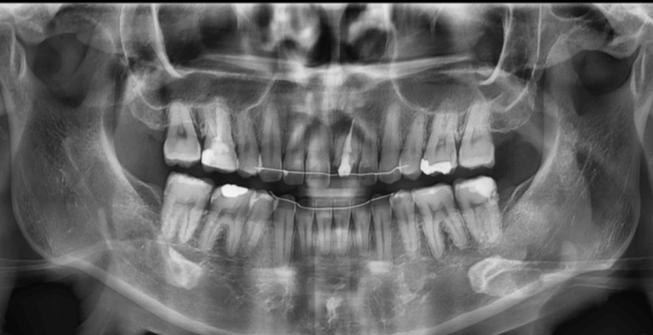

口元の突出感が気になる

| 年齢・性別 |

25歳の女性 |

|---|---|

| 主訴 | 口元の突出感を気にされて来院された。咬み合わせや審美的な改善を希望されていました。 |

| 治療期間・回数 | 3年6ヶ月・30回 |

| 費用 | 1,000,000円 |